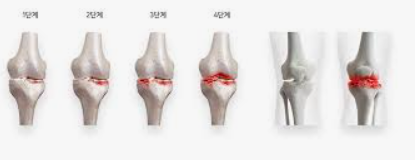

퇴행성 관절염, 일명 '골관절염'은 관절을 보호하는 연골이 닳아 없어지면서 발생하는 질환입니다. 이로 인해 관절의 뼈가 서로 마찰을 일으키며 통증, 부기, 그리고 운동 범위의 제한을 초래합니다. 퇴행성 관절염은 주로 노화와 관련이 있으며, 무릎, 엉덩이, 손, 그리고 척추와 같은 관절에 자주 나타납니다.

증상은 점진적으로 발전하며, 초기에는 운동 후 통증이 나타나기 시작합니다. 시간이 지남에 따라 휴식을 취해도 통증이 지속되며, 관절의 경직과 부기가 동반됩니다. 심한 경우에는 관절의 변형까지 발생할 수 있습니다. 날씨가 추울 때나 습할 때 통증이 더 심해지는 것을 경험할 수도 있습니다.